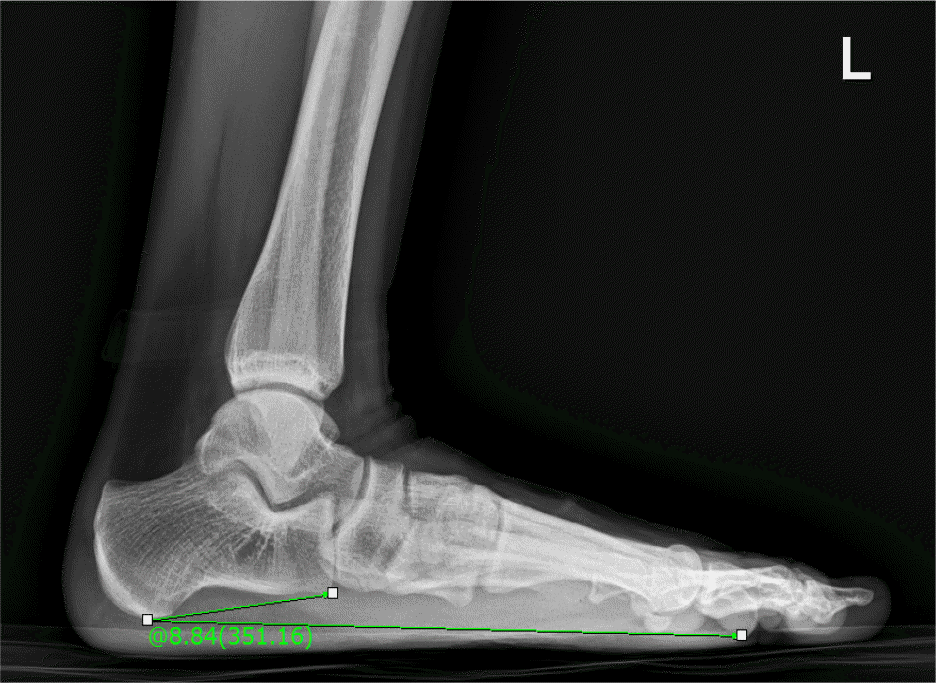

Comparison of ankle range of motion, functional ability and talar tilta

| Variables | FDG (n=8) | NCG (n=10) | t | df | Pb |

|---|---|---|---|---|---|

| Range of motion | |||||

| PF, ○ | 82.75±5.52 | 92.60±8.69 | –2.778 | 16 | 0.013 |

| DF, ○ | 19.37±6.20 | 21.30±8.98 | –0.514 | 16 | 0.614 |

| Functional ability | |||||

| Balance test, s∗ | 32.37±26.75 | 38.50±16.47 | –0.598 | 16 | 0.558 |

| Side step test, times/20 s | 16.12±1.12 | 16.40±1.17 | –0.503 | 16 | 0.622 |

| Talar tilt, ○ | 6.57±2.95 | 3.70±2.42 | 2.266 | 16 | 0.038 |